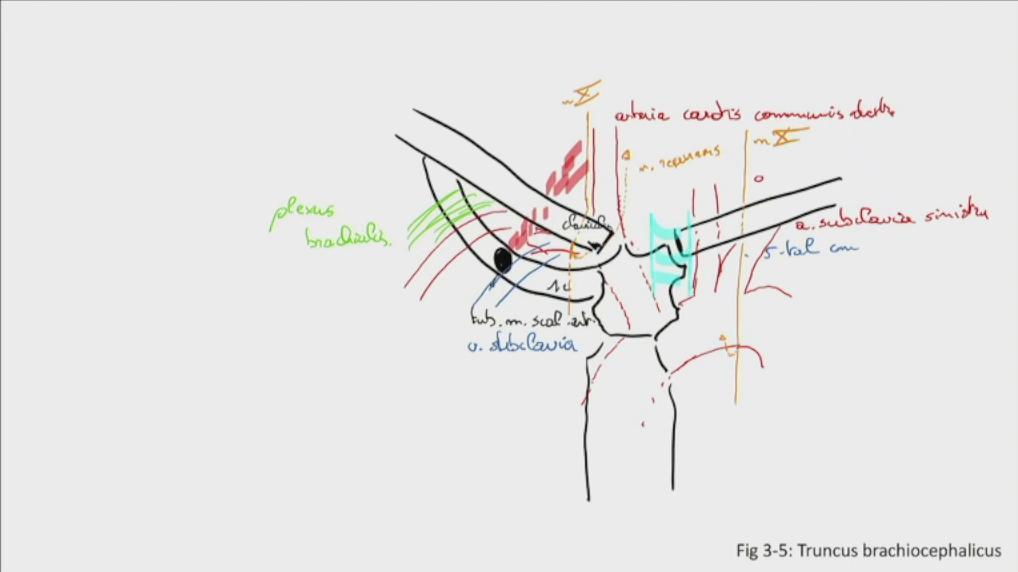

Fig 3.05: tr. brachiocephalicus

sternum clavicula rib I trachea (cyaan) tuberculum m. scalenus anterior m scalenus anterior plexus brachialis -

zijtakken tr. brachiocephalicus

a carotis communis dextra a subclavia dextra (uit achterste scalenuspoort)

v subclavia dextra (uit voorste scalenuspoort) a carotis communis sinistra (herhaling) a subclavia sinistra (herhaling) linker n vagus + n recurrens (herhaling) -

rechter n vagus (X)

-

rechter n vagus > rechter n laryngeus recurrens = n recurrens